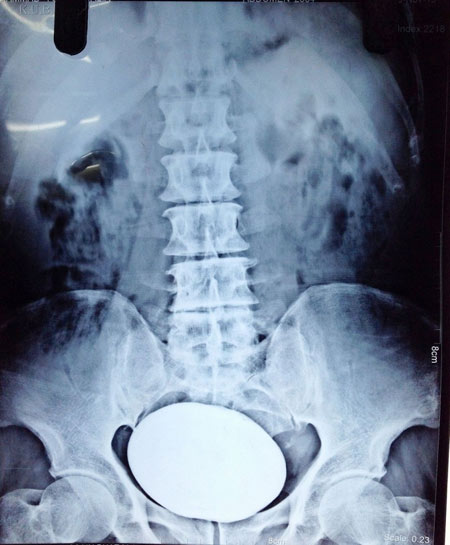

Ảnh chụp hòn đá nằm trong bàng quang bệnh nhân trước khi phẫu thuật.

Bác sĩ xác nhận, hòn đá nặng 834g, lớn nhất từng được lấy ra từ bàng quang của bệnh nhân.